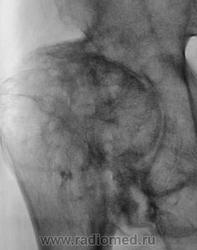

"Спинальный больной". Наблюдение Бородулина М.А. Наблюдение Бордулина М.А. Наблюдение Катенёва В.Л. Пт, 06/07/2012 - 21:41 #1 Наталия Васильевна Не на сайте Был на сайте: 5 лет 7 месяцев назад Зарегистрирован: 25.09.2011 - 09:02 Публикации: 754 А возможны ли такие изменения при сирингомиелии? Пт, 06/07/2012 - 22:22 #2 Катенёв Валенти... Не на сайте Был на сайте: 6 лет 11 месяцев назад Зарегистрирован: 22.03.2008 - 22:15 Публикации: 54876 По всей видимости - да. Пт, 06/07/2012 - 23:03 #3 И.Бондаренко Не на сайте Был на сайте: 1 день 9 часов назад Зарегистрирован: 13.09.2011 - 22:55 Публикации: 9199 Считайте ,что такие изменения сопутствуют сирингомиелии. Пт, 06/07/2012 - 23:08 #4 Катенёв Валенти... Не на сайте Был на сайте: 6 лет 11 месяцев назад Зарегистрирован: 22.03.2008 - 22:15 Публикации: 54876 И.Бондаренко wrote: Считайте ,что такие изменения сопутствуют сирингомиелии. +1 Сб, 07/07/2012 - 22:10 #5 Наталия Васильевна Не на сайте Был на сайте: 5 лет 7 месяцев назад Зарегистрирован: 25.09.2011 - 09:02 Публикации: 754 Ну, тогда, действительно-"спинальный больной".

А возможны ли такие изменения при сирингомиелии?

По всей видимости - да.

Считайте ,что такие изменения сопутствуют сирингомиелии.

Ну, тогда, действительно-"спинальный больной".